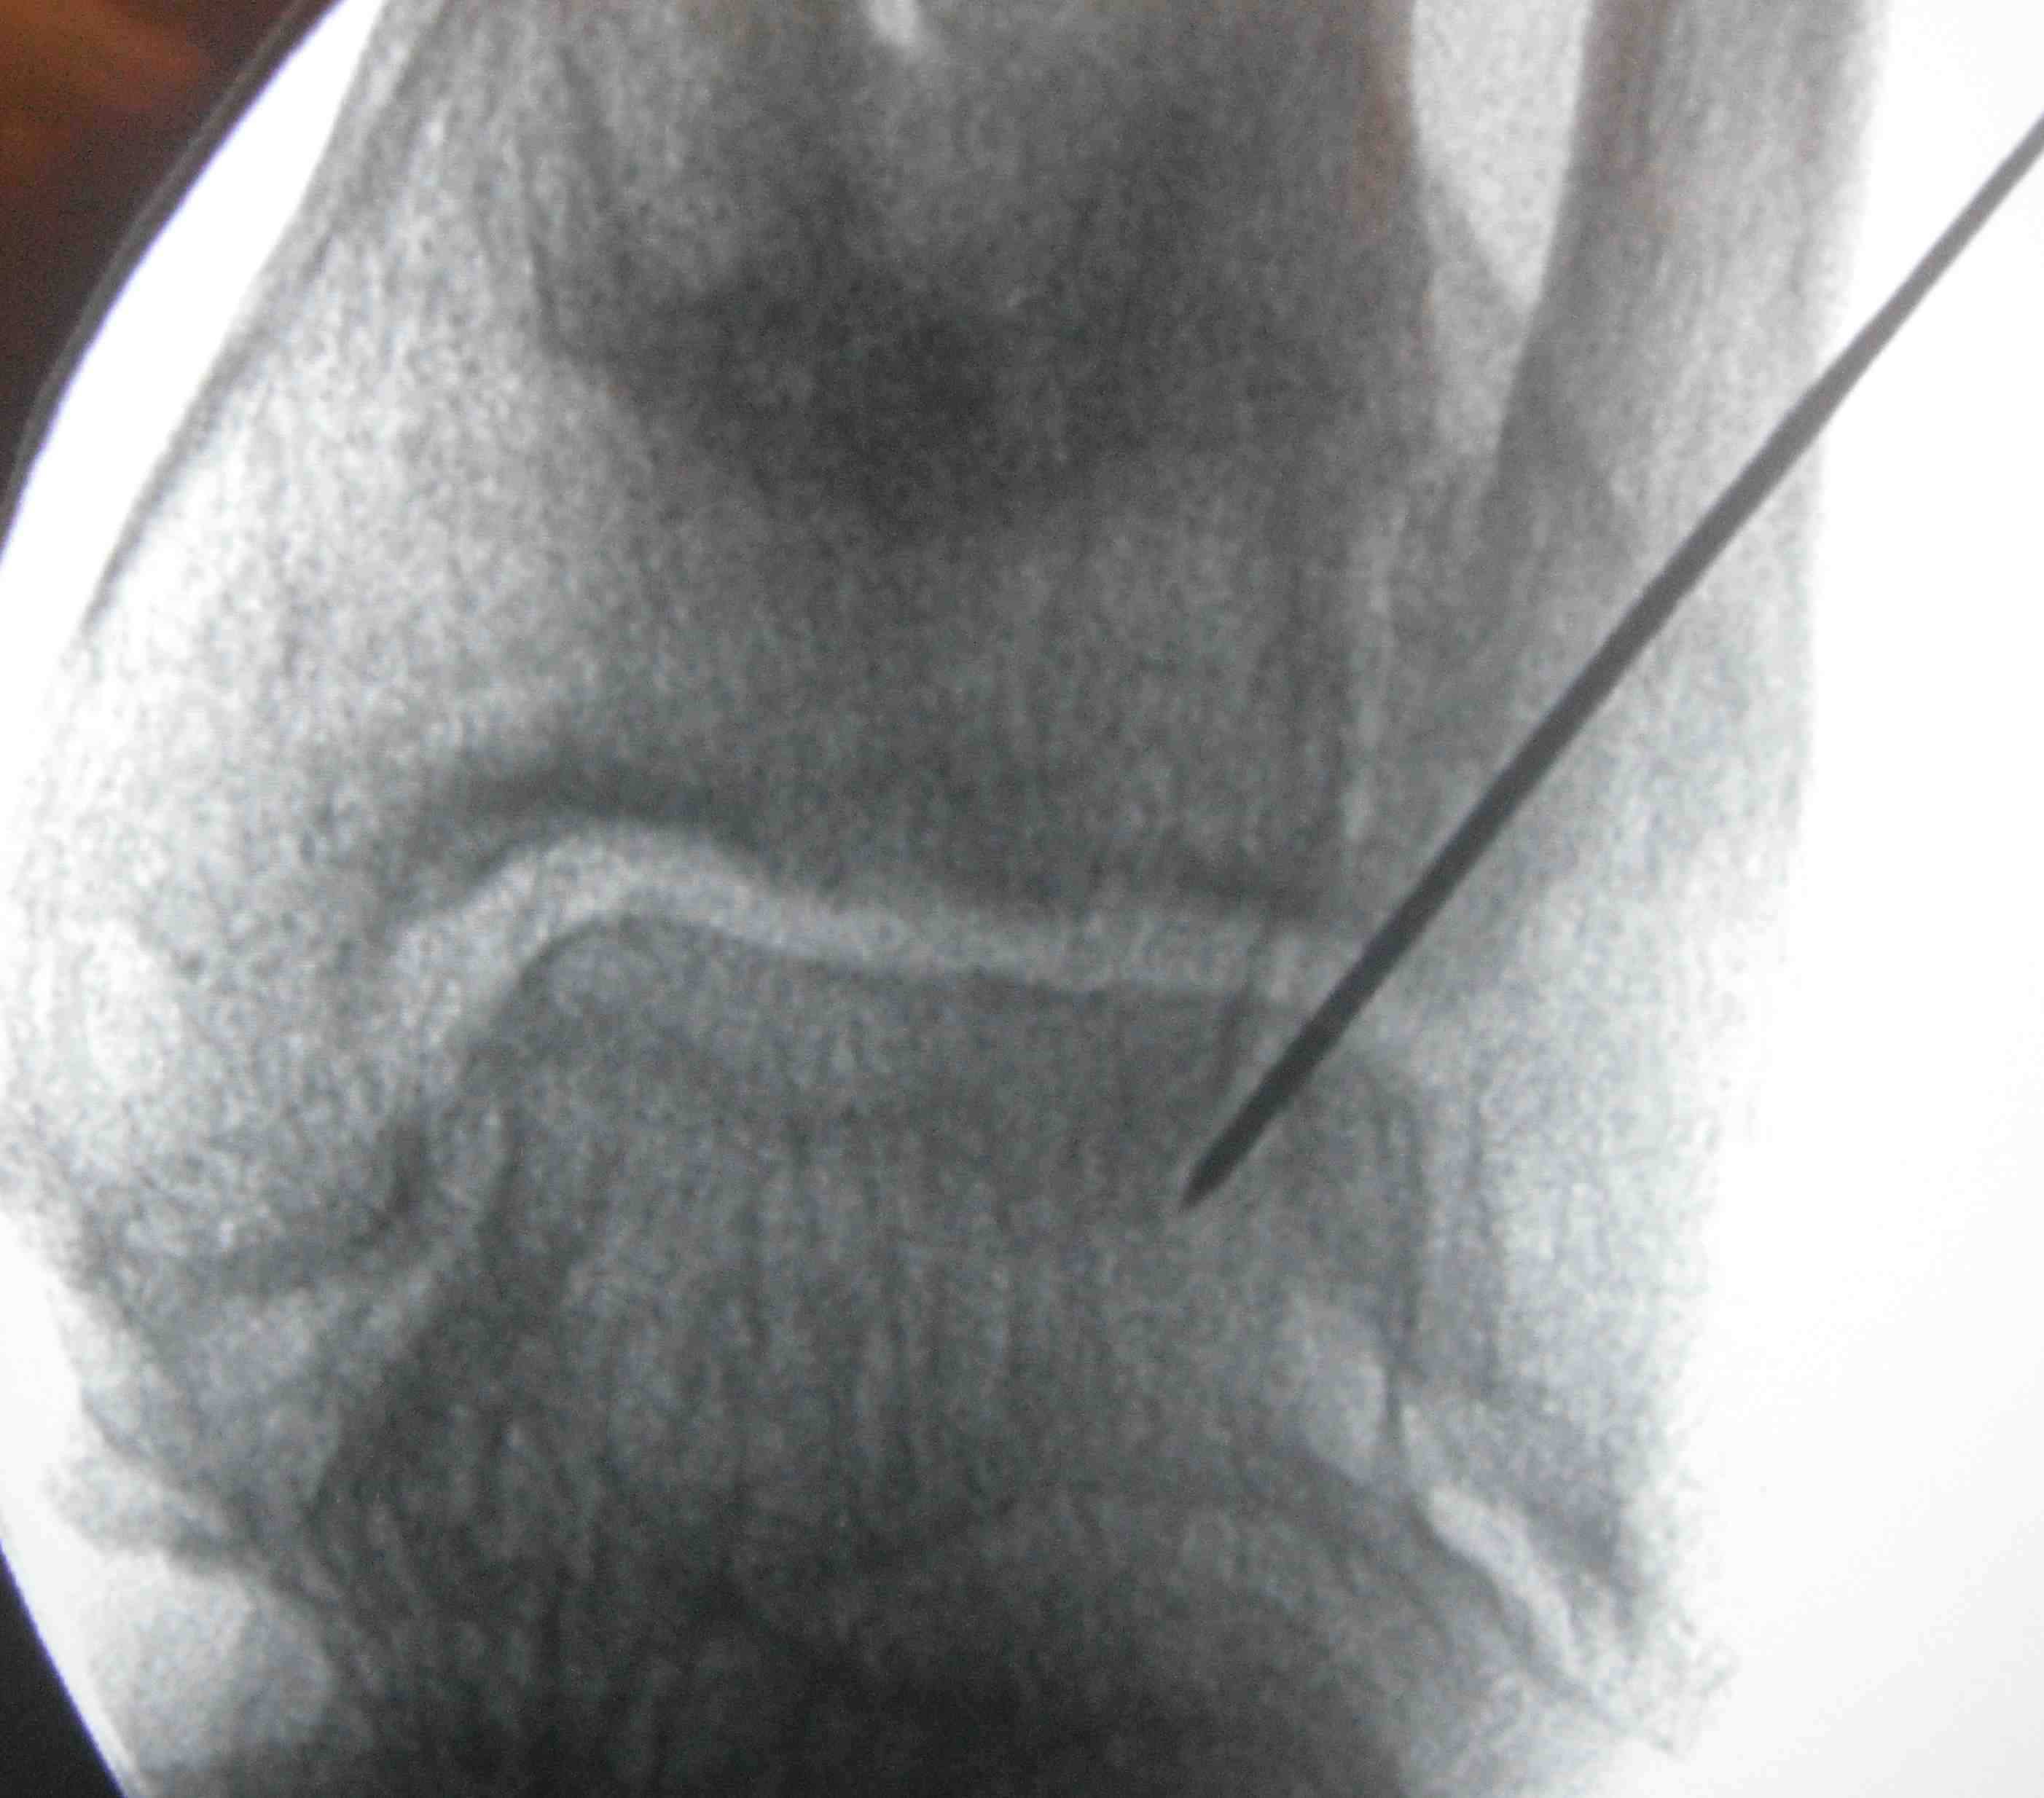

- position foot, check with image intensifier

- neutral dorsiflexion, slight eversion / slight external rotation

- fix with 3 x 6.5 mm cannulated screws

- 2 medial and one lateral